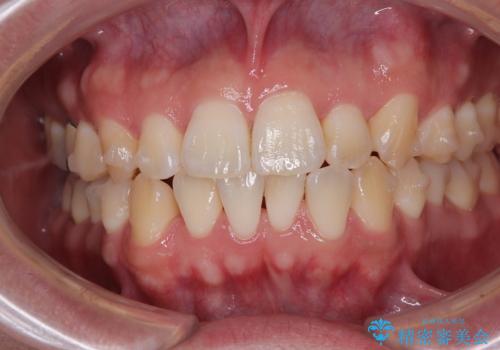

- 前歯の反対咬合などを気にして来院された患者様です。

ワイヤー矯正、マウスピース矯正どちらでも対応可能であったので、ご本人の希望によりインビザラインにて矯正治療を行うこととしました。

マウスピース矯正は、ワイヤー矯正と違い、とにかく自己管理が非常に重要となります。

毎日の装着時間をしっかりと守ってくださり、1年強の短期間で、あっという間に治療を終えることができました。